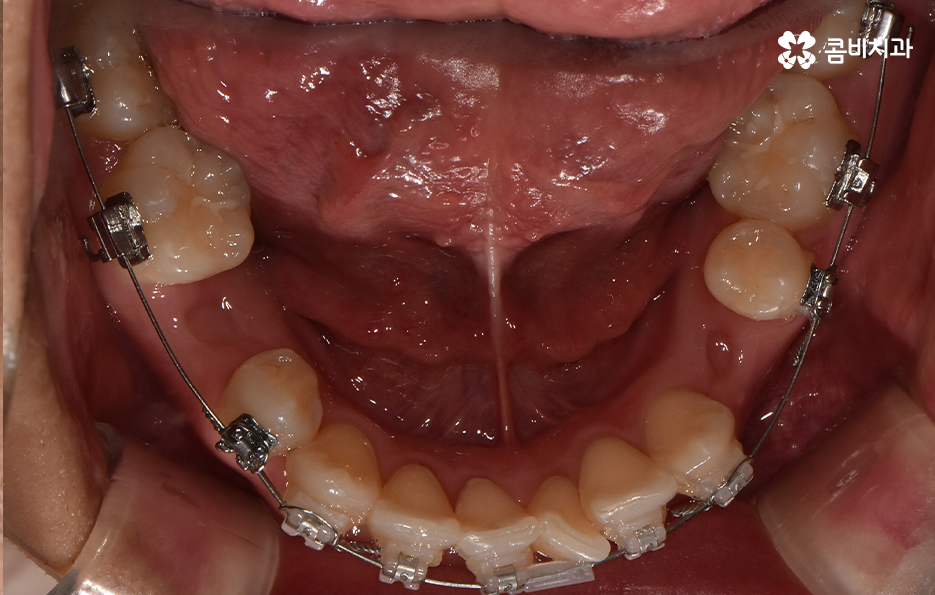

덧니가 나는 원인은 유전적인 영향부터 골격적인 부분 등 다양하지만 기본적으로는 치아가 나올 공간이 부족해서 덧니의 형태로 영구치가 자라는 경우가 많기 때문에 덧니 교정 사례에는 유독 발치 교정 사례가 많이 있는데요

다만 덧니 교정 사례에서 발치교정 사례가 많은 이유는 턱뼈가 좁아서 치아가 덧니로 자란 경우가 많기 때문에 치열을 재배열하기 위해서는 치아가 움직일 수 있는 충분한 이동공간이 필요하기 때문에 공간 확보의 목적으로서 작은 어금니 양옆, 위아래 4개를 발치를 하는 발치교정법이 보편적으로 많이 활용되고 있으며 치아의 이동 공간을 확보하는 방법으로는 발치 교정법 외에도 악궁확장, 어금니 후방이동, 치간삭제와 같은 비발치적인 방법도 가능하기 때문에 치아를 얼마나 이동시켜야 할지에 따라서 치료법은 개인차가 발생되고 있어요

발치교정이 필요한지 여부에 대한 판단은 치아의 이동 공간이 얼마나 필요하고 확보해야 하는지에 따라 달라지는데 이러한 판단 근거는 단지 치열만을 두고 보는 것이 아니라 골격과 얼굴형을 종합적으로 고려한다는 점에서 정밀검진과 함께 풍부한 경험을 갖춘 교정 전문의와 잘 상의하여 결정하신다고 보시면 될 거예요